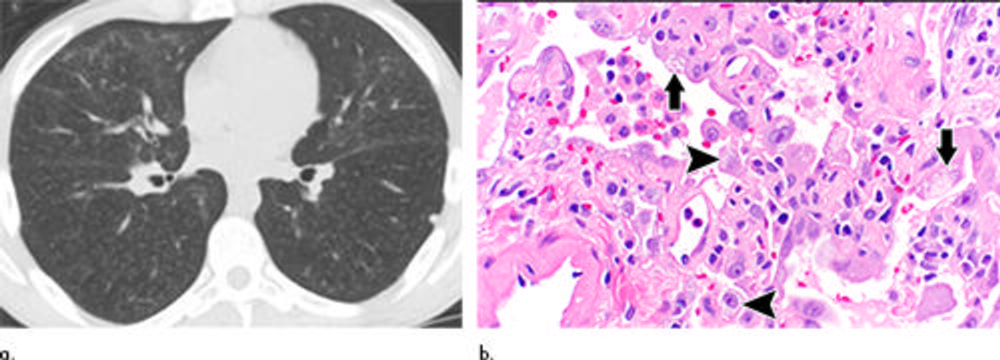

Figure 4. Electronic cigarette or vaping product use–associated lung injury in a 21-year-old man manifesting as a nonfibrotic hypersensitivity pneumonitis pattern at CT that subsequently completely cleared. (a) Axial unenhanced CT image obtained 3 days after presentation shows diffuse, poorly defined centrilobular ground-glass opacity nodules; the CT pattern resembles nonfibrotic hypersensitivity pneumonitis. (b) Histopathologic findings show finely vacuolated foamy macrophages (arrowheads) as well as vacuolated type II pneumocytes (solid arrows) (Hematoxylin-eosin stain, magnification, ×60).